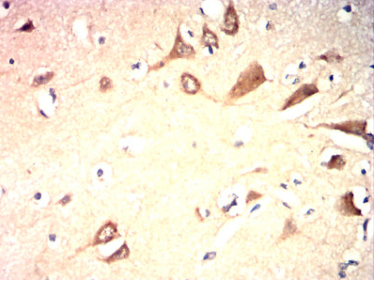

IHC    1/200 - 1/1000